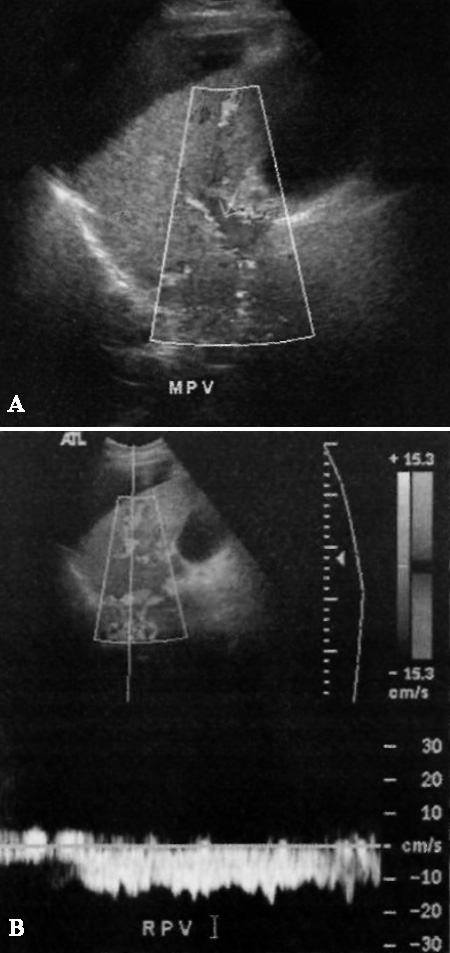

В воротной вене гепатопедальный кровоток (направлен в сторону печени) демонстрирует монотонную постоянную форму. На цветовой допплерографии сигнал заполняет всю площадь просвета сосуда, что дает основание исключить тромбоз воротной вены (может быть анэхогенным). Спектральная допплерография демонстрирует низкую скорость потока (15-40 см/с), который может быть двунаправленным в результате завихрений, возникающих в крупных венах с медленным кровотоком. Гепатофугальный (обратный) кровоток по воротным венам определяется при портальной гипертензии, если портосистемные анастомозы хорошо функционируют (фото 2).

Допплерография: Воротная вена печени

Фото 2. Воротная вена печени в норме. А – цветовая допплерограмма правой ветви воротной вены: определяется гепатопедальный кровоток. В – пульсовая кривая воротной вены в норме